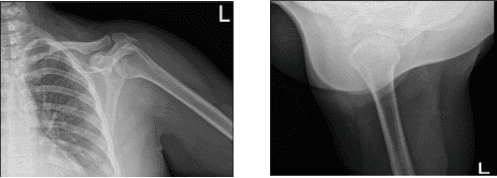

Se revisaron radiografías y se discutió que su hombro izquierdo mostraba radiografías normales. Aconsejamos al paciente que se hiciera una resonancia magnética para ver la causa y descubrimos una rotura de grosor parcial del tendón subescapular, aunque no hay desgarro de alto grado parcial o total del manguito rotador. Presencia de tendinosis supraespinosa e infraespinosa.

Radiografía del hombro izquierdo